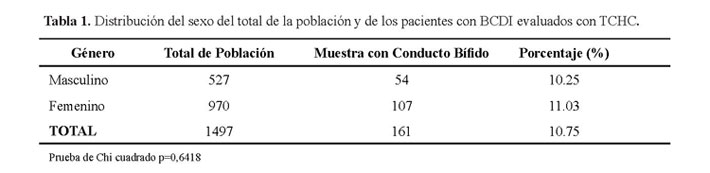

Se revisaron 1497 tomografías de los cuales 10.75% (161 casos) presentaron bifurcación del conducto dentario inferior. En la población el género femenino fue el 64.8% (970 casos) y el género masculino fue el 35.2% (527 casos). La prevalencia de la BCDI en el género femenino fue de 11.03% (107 casos) y en el masculino fue de 10.2% (54 casos) (Tabla 1).